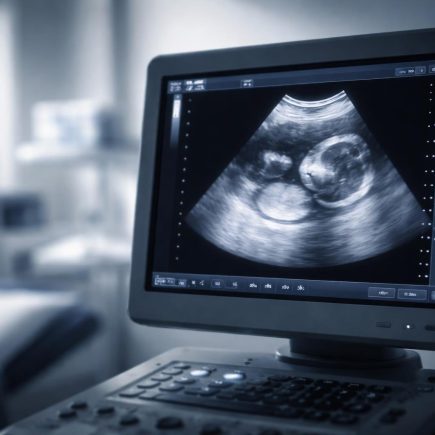

Écho 9SA : Que Voit-on à l’Échographie ?

Vous arrivez à votre examen et vous vous demandez ce qui va apparaître sur l’écran ? Est-ce que le bébé ressemble déjà à un petit humain ? Est-ce qu’on peut entendre son cœur battre à ce stade ? L’échographie à 9 SA (semaines d’aménorrhée) est un moment charnière où l’embryon commence sa mutation pour devenir …

Écho 6SA : Que Voit-on sur l’Échographie ?

Vous attendez votre première échographie de datation avec un mélange d’impatience et d’appréhension ? Vous vous demandez ce qu’il est réellement possible de voir sur l’écran à ce stade précis ? Est-ce normal de ne pas encore distinguer de forme humaine ou d’entendre le cœur ? Cet article vous explique en détail ce que votre …